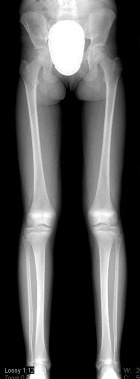

K.M. - 13 year old female with a painful soft tissue mass of the left anterior knee